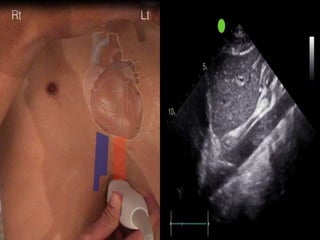

Technique

• We use low frequency probe or abdominal

probe.

• The transducer position is just below the

xiphisternum 1-2 cms to the right of midline

with the marker dot pointing towards the

sternum notch.

• M-mode line is placed through the IVC

2-3cms from the junction between IVC and

right atrium or 0.5-1 cm from the junction

of hepatic vien.

Technique • We uselow frequency probe or abdominal probe. • The transducer position is just below the xiphisternum 1-2 cms to the right of midline with the marker dot pointing towards the sternum notch.

• M-mode lineis placed through the IVC 2-3cms from the junction between IVC and right atrium or 0.5-1 cm from the junction of hepatic vien.